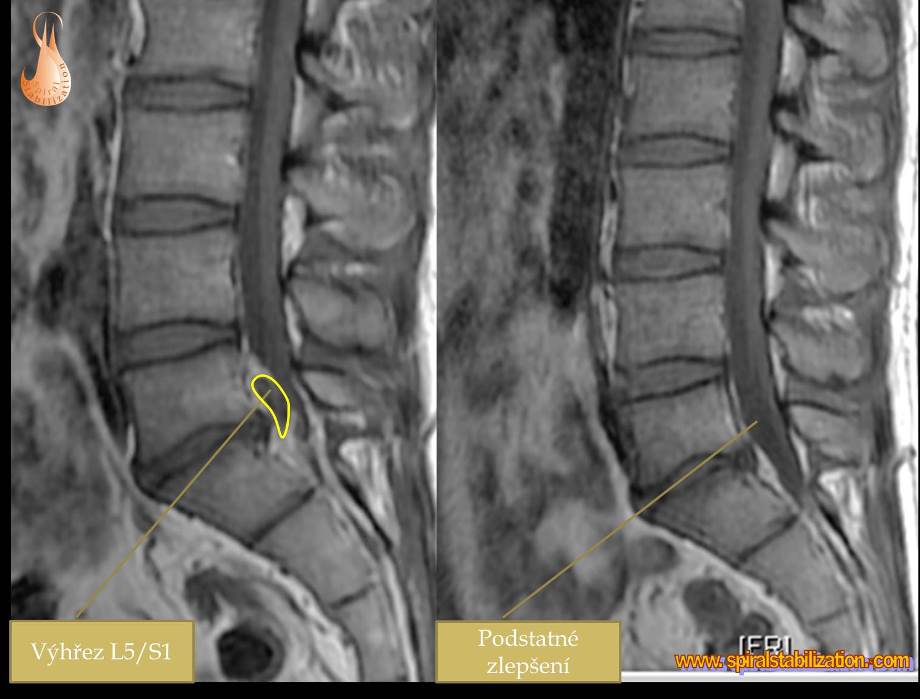

Výsledky hernia L5/S1